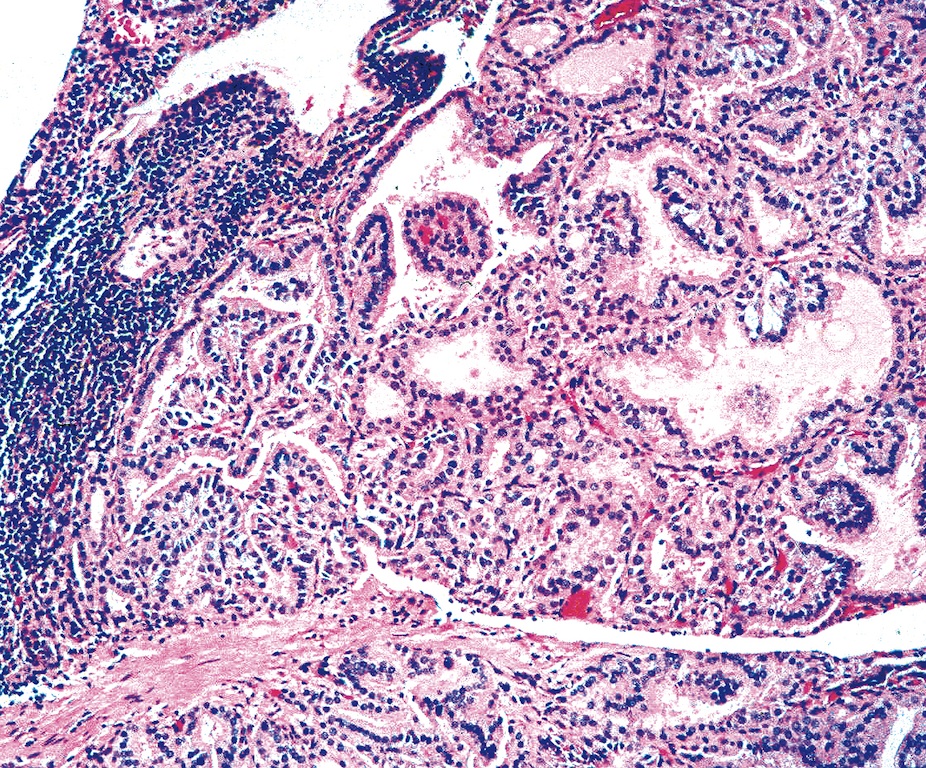

• Hyperplastic thyroid follicles with papillary infoldings

• Diffuse hyperplasia and hypertrophy of follicular cells with retention of lobular architecture and prominent vascular congestion

• Tall follicular cells with papillae usually lacking fibrovascular cores

• Nuclei are round, often basally located, rarely overlap

• Colloid is typically decreased, when present shows peripheral scalloping

• Variable patchy lymphoid infiltrate in the stroma

Diffuse hyperplasia with well developed papillae

Follicular cells lining papillae are tall and columnar

Hyperplastic small follicles